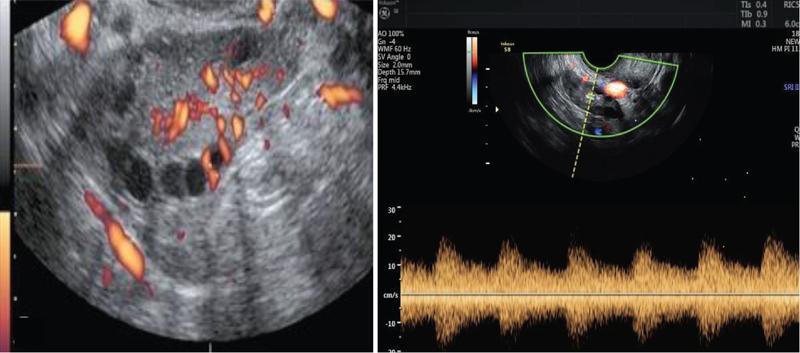

Ovarian stromal blood flow

• Ovarian stromal blood flow reflects the percentage of gonadotropins in systemic circulation that reaches the ovary

• Stromal blood flow should be assessed in the middle of ovarian stroma

• Spectral Doppler with or without 3D power Doppler study of stromal blood flow has to be done (Fig. 11.20.1.7)

• Depending on the Doppler values, the patients can be categorized as:

• Hyperresponders: RI <0.48; PSV >10 cm/s

• Normal responders: RI 0.5 to 0.7; PSV – 5 to 10 cm/s

• Poor responders: RI >0.7; PSV <5 cm/s

• In hyperresponder, the dosage of gonadotropin required for stimulation is less whereas in poor responder, the dosage required is more

• Vascularity index (VI), flow index (FI) and vascular flow index (VFI) are assessed using 3D power Doppler

• In poor responders (stromal flow index <11), recombinant LH may be added

Image

Fig. 11.20.1.7 Spectral Doppler study of ovarian stromal blood flow.